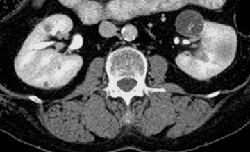

RADIOLOGY: GASTROINTESTINAL: GI: Case# 33021: BILATERAL CYSTS WITH PAPILLARY HYPERPLASIA